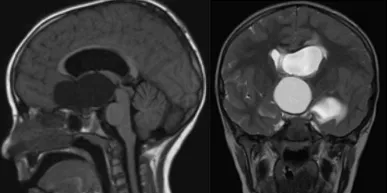

等到家属带着拉拉来到医院时,孩子更是出现了视力问题。这下病情非同小可,在进一步检查下,拉拉竟被查出了一个骇人的脑瘤。它像一颗巨型弹珠,就这样圆滚滚地住进了女孩的脑中,也令拉拉一家倒吸了口凉气——接下来要怎么办?

教授表示,由于拉拉的肿瘤属于囊性颅咽管瘤,因此他可以尝试不做开颅手术,而是通过囊肿分流的方式缩小肿瘤体积。拉拉家属接受了这一建议,不久后,拉拉正式接受治疗。

鲁特卡教授及团队通过插入VP分流器和Ommaya囊来实现,并在不断拍打Ommaya储液囊后,效果十分明显——拉拉的颅咽管瘤肉眼可见地缩小,甚至几乎消失无踪!